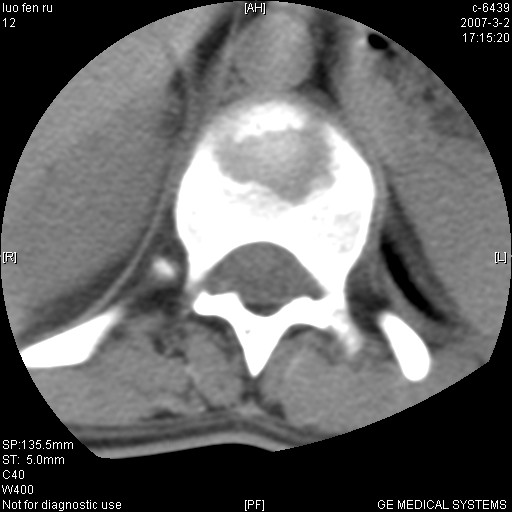

标题: CT6952:T11椎体病变请讨论

女,19岁.背部疼痛一月余.自诉幼时有个外伤史.

腰椎平片示,t11椎体呈楔形改变,椎间隙未见异常.

支持胸11椎体中央型结核。

病人病史不长,病变表现比较明显,如果是结核,病史不支持,椎间隙不窄,临近椎体正常,椎旁无冷浓疡,但从病变本身硬化也较多,均不太支持结核。慎重考虑的话,可以问一下病人有无结核病史。如果没有,更多的应该考虑陈旧性骨折,伴有慢性椎间盘炎可能。确诊后记着告知啊!

第一感觉就像嗜酸性肉芽肿,骨折及tb不能解释表现

t11椎体前缘不规则形骨质破坏,周围有硬化边,软组织肿块不明显,首先考虑:骨嗜酸性肉芽肿 。期待随访结果。